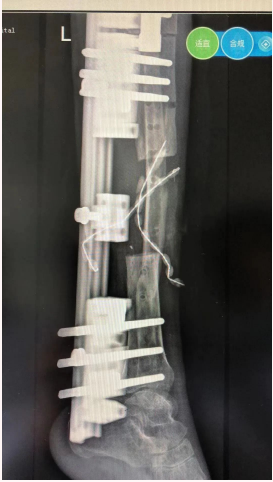

患者X先生,男,31岁,2年前因左侧开放性、粉碎性胫腓骨骨折在江苏宁波某医院住院治疗,充分术前准备后行手术治疗;术后,患者左小腿感染流脓,虽经4次手术,但未见好转,遗留慢性骨髓炎、骨质外露。加之经常有脓液流出,伤口周围皮肤疤痕发黑,每因行走或劳累后患肢疼痛,肿胀加剧,只得扶拐跛行,随后丧失劳动力,被迫返乡,辗转多家医院救治依然无效,伤病严重影响生活,也给其心理带来创伤。

到我院创伤外科住院后,副主任王磊及其团队医护进行详细诊查,针对病因抗炎、换药治疗。期间,王磊带领团队评估伤情、翻阅资料、咨询专家,经多次商议和手术模拟,最终确定手术方案,并实施“搬运手术”。

经术前充分准备,手术过程顺利,术后患者整体情况良好,感染的伤口恢复良好,现骨缺损部分正在逐步生长愈合中。X先生对后续治疗恢复充满信心,笑容逐渐满布脸颊,身体好,心理也好,以后的生活会更好!

骨搬运技术是通过人为方法把骨头切断造成骨折后,在骨折的远近两端安上外固定支架,通过上面的特殊装置,以持续缓慢牵引,向两端延长,延长所产生的空间会通过人体的自然重建功能而生成新骨(称之为牵张成骨)。目前,作为一个被确定的、公认的手术方式,被广泛的应用在各种疾病的治疗中。